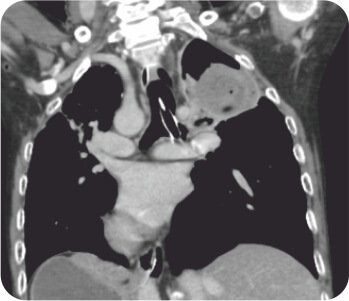

CT chest with thoracic angiogram revealed bilateral cavitary lesion with hypertrophied collateral arteries predominantly supplying the right upper lobe cavity. FOB done showed active bleeding from right upper lobe bronchus.

Pre procedure CT Scan

CT thoracic angiograph